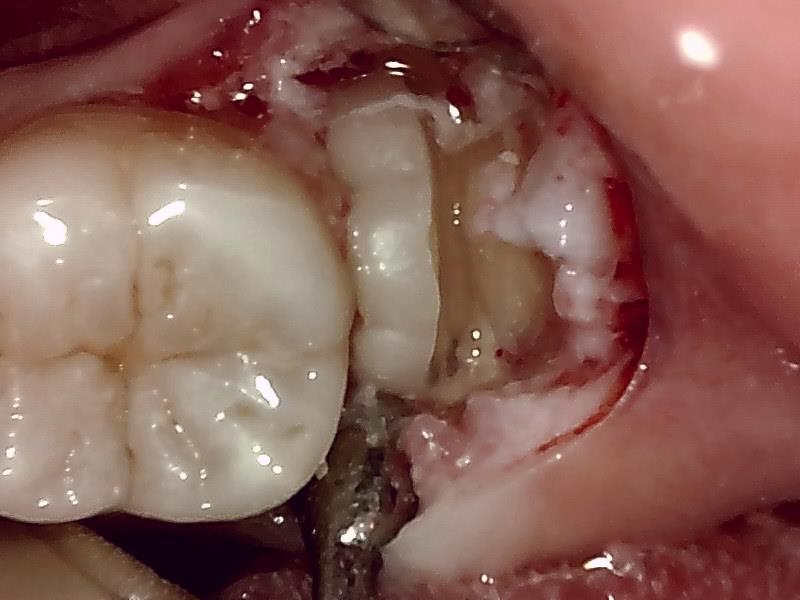

歯牙分割して除去

抜歯窩

この抜歯法により術後の腫れ痛みが大幅に軽減されます。

抜歯後、経過良好です。